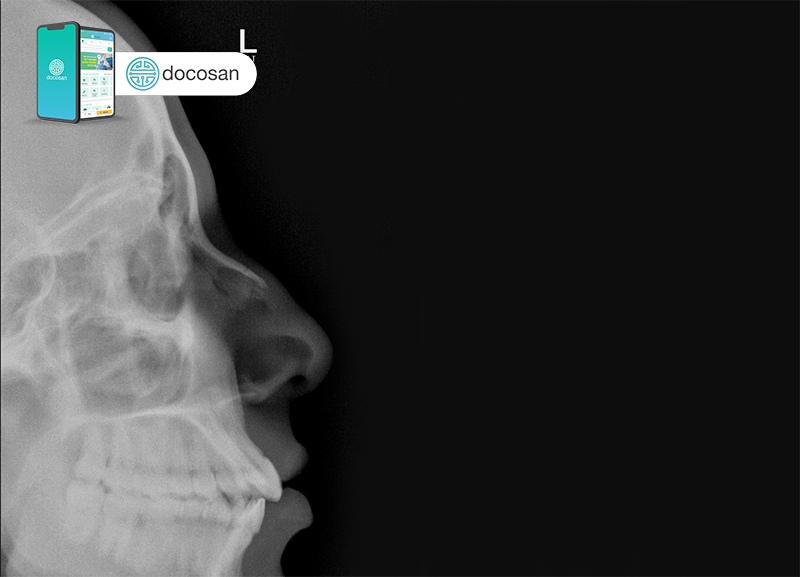

- Khám sức khỏe: Bác sĩ sẽ thực hiện một số xét nghiệm cơ bản và kiểm tra các đặc điểm trên khuôn mặt của bạn, bên trong và bên ngoài mũi. Khám sức khỏe giúp bác sĩ xác định các đặc điểm thể chất chẳng hạn như độ dày của da hoặc độ bền của sụn ở cuối mũi. Những yếu tố này có thể ảnh hưởng đến kết quả và xác định tác động chỉnh hình mũi đối với hô hấp.

- Hình ảnh: Bác sĩ phẫu thuật có thể chụp hình và sử dụng phần mềm máy tính để mô phỏng kết quả.